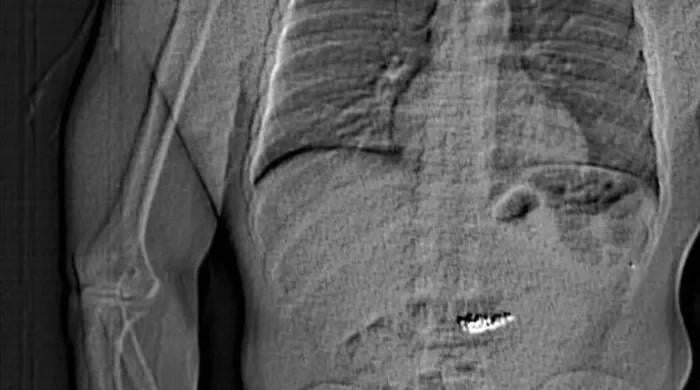

A handout image of an x-ray released by the Orlando Police showing an abdomen with a…